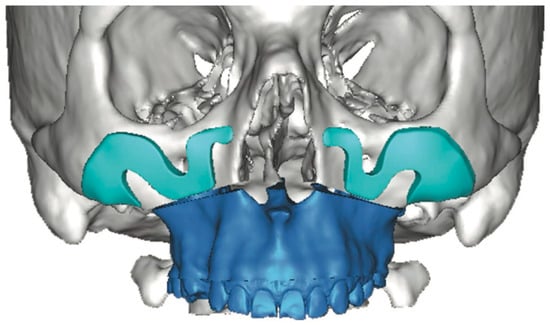

CAD/CAM-designed patient-specific implants (PSIs) enable greater precision and planning, particularly in complex or asymmetric facial cases, offsetting increased cost and planning time by reducing surgical duration and improving esthetic predictability [21,26]. Unlike stock implants, which often require intraoperative trimming and risk asymmetry, PSIs provide faster, more predictable symmetry and volumetric restoration. Screw fixation—usually one or two per implant—ensures stability and prevents postoperative displacement [21]. However, the design of customized implants must account for the practical feasibility of intraoperative positioning and stabilization. If these considerations are overlooked, the implant may not be clinically executable when transitioning from virtual planning to surgical application (Figure 4). Therefore, the surgeon must closely monitor and actively participate in the design process to ensure that the final construct is surgically achievable.

Figure 4. Three-dimensional computer-assisted design illustrates the potential for highly customized implant geometry. However, in this case, the virtual planning lacked adequate anatomical assessment and did not include a rigorous evaluation of the surgical access or the feasibility of implant insertion within the available soft-tissue pocket. These oversights contributed to limitations in the clinical applicability of the proposed design—Image from the authors’ personal archive.